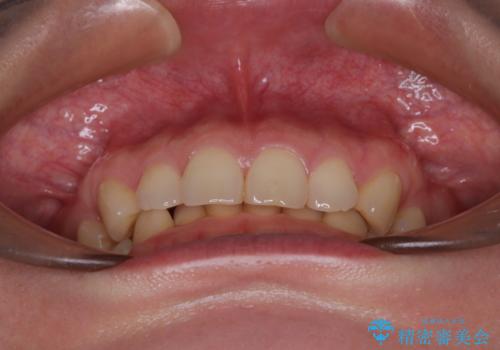

隠れた前歯が気になる ディープバイトのワイヤー矯正治療

下顎臼歯を起き上がらせるためにユーティリティーアーチを使用し、一気に深い咬み合わせを改善することができました。